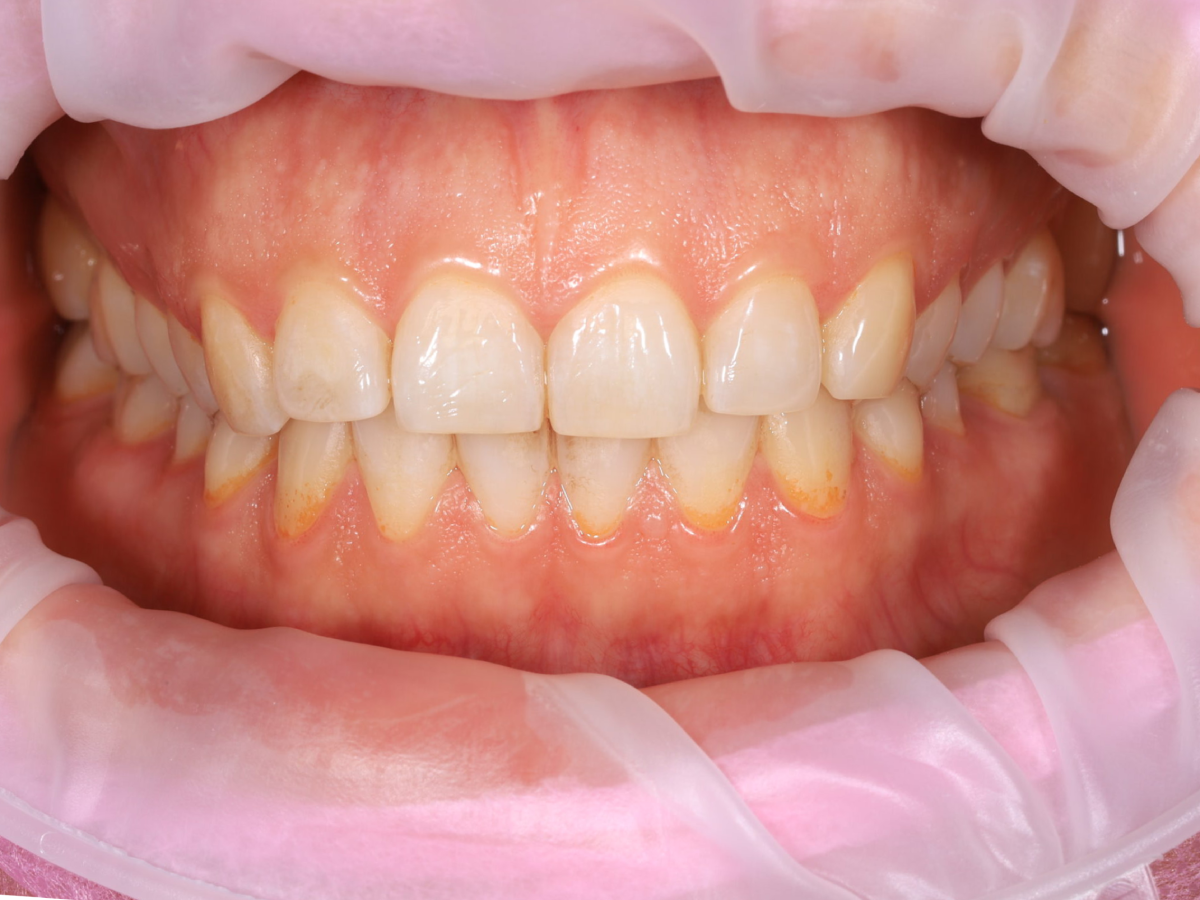

Pełna higienizacja: usunięcie kamienia i osadu (scaling, piaskowanie).

Profesjonalne czyszczenie zębów: scaling, polerowanie i fluoryzacja.

Metamorfoza uśmiechu: usunięcie przebarwień i kamienia nazębnego.